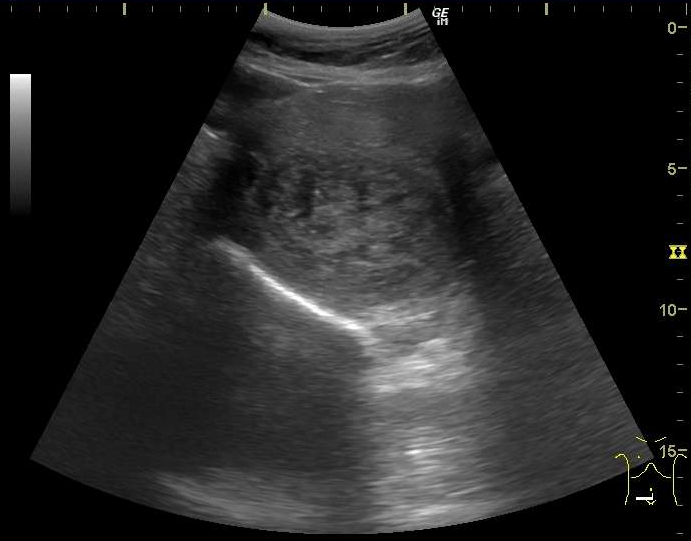

これまでの超音波画像診断装置(エコー)を使った健診の様子、第5回は、チンパンジーのアキナです。

アキナ(チンパンジー、32歳、女)

子宮筋腫の超音波断層像

子宮筋腫は多くの高齢雌に見られますが症状は様々で、ひどい場合はうずくまって歩けなくなることもあります。